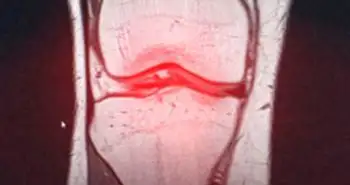

Тяжелое течение периодонтита может быть связано с развитием артроза у определенных групп пациентов с сахарным диабетом 2-го типа. Такие выводы были сделаны по результатам исследования, прошедшего при участии 3,5 тыс. человек.

По словам исследователей, полученные ими данные могут свидетельствовать о том, что воспаление в полости рта при периодонтите может быть вовлечено в патогенез артроза, особенно у пациентов с сахарным диабетом 2-го типа.

Исследование проводилось с использованием данных 3527 участников (≥50 лет), собранных в 2008–2015 гг. После коррекции данных по полу, возрасту, ИМТ, потреблению алкоголя, курению, уровню образования, уровню физической нагрузки, доходу, наличию артериальной гипертензии и частоты чистки зубов, было выявлено, что у пациентов с сахарным диабетом 2-го типа чаще развивается артроз при наличии тяжелого воспалительного процесса в полости рта.

Статистически значимая корреляция не была отмечена среди лиц без сахарного диабета 2-го типа даже после поправки по указанным факторам.

Авторы работы заявили о необходимости проведения дополнительных исследований для определения точного механизма связи периодонтита и артроза.